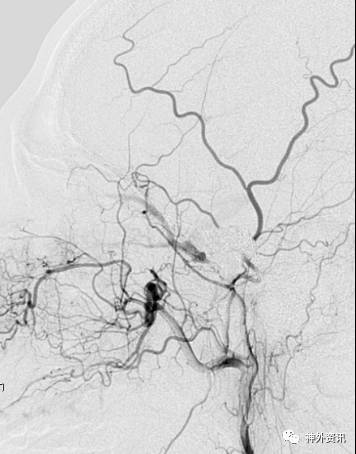

复合立体塑形

塑形考虑血管走行,但是血管内径过大(约>3mm,例如颈内动脉)的情况下,微导管在血管内是螺旋前进(2维是折线前进),即使顺行也需要考虑改变角度。

非同一平面内的弯曲:

(1)指向前方或后方的前交通动脉瘤

(2)指向前方或后方的大脑中动脉分叉部位动脉瘤

病例一